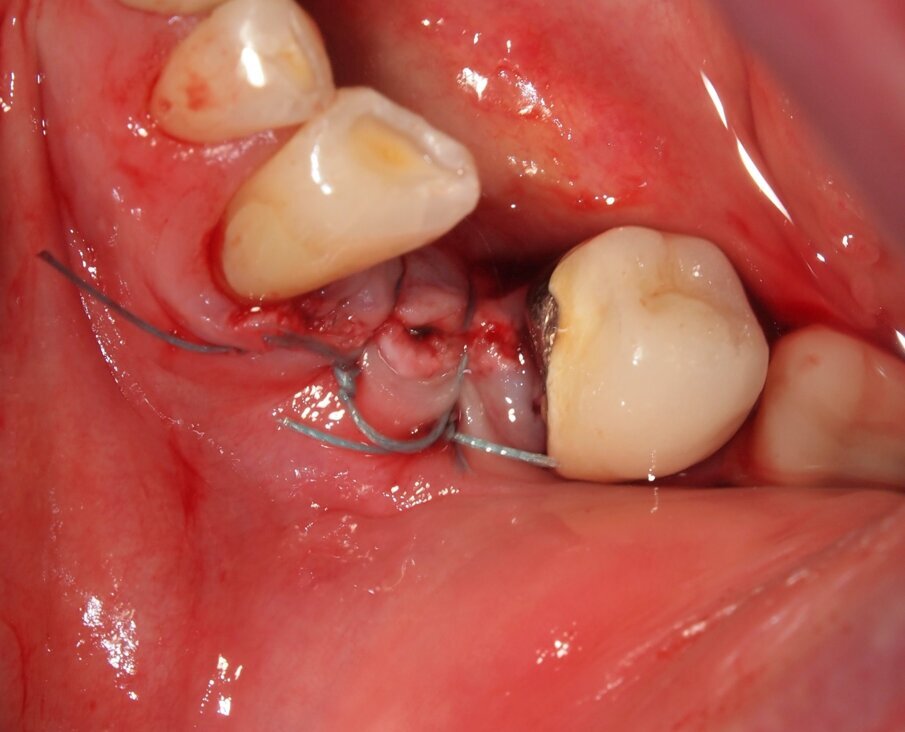

Fig. 6 - Caso clinico 1. Sollevamento di un lembo mucoperiosteo ed esposizione della corticale ossea. Si apprezza macroscopicamente l’assenza di fenomeni di carbonizzazione e danni termici dei tessuti molli e del tessuto osseo che mantiene un’adeguata vascolarizzazione.

Fig. 8 - Caso clinico 1. Sutura di riposizionamento in poliammide 4/0.